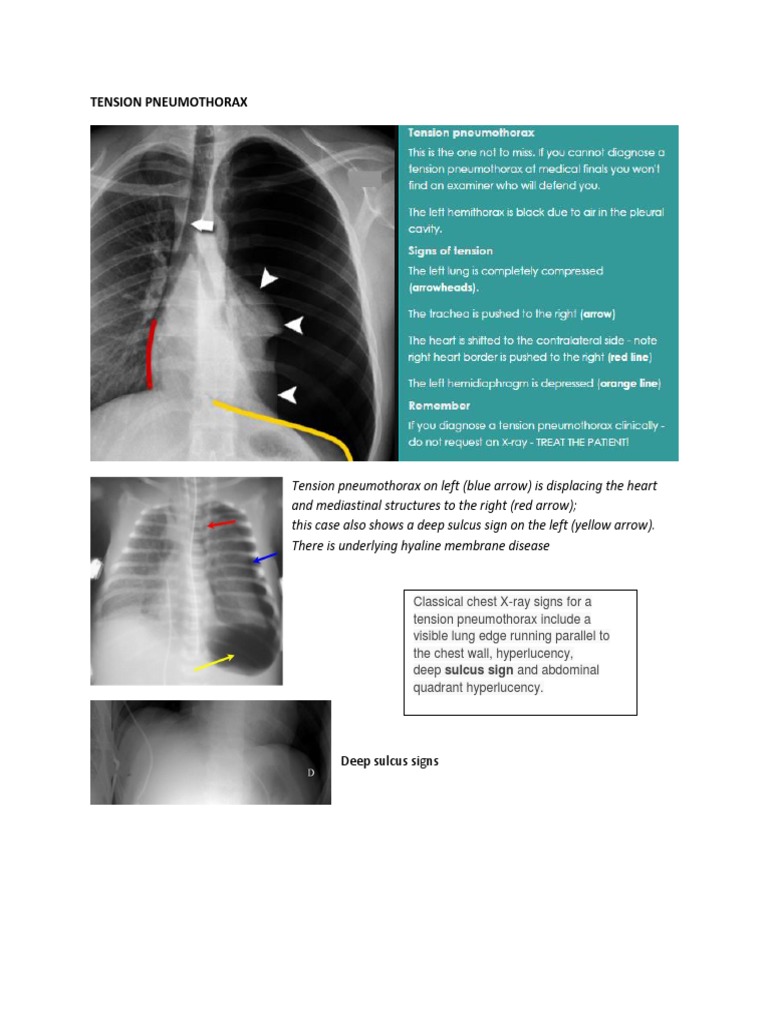

Rc Students Club On Twitter Pneumothorax 1 Air Found In The Pleural Cavity Appears Dark With No Vascular Markings In The Involved Areas Tension Pneumothorax May Result In A Mediastinal Shift

غدير الموسى On Twitter Tension Pneumothorax Must Be Recognized Without Delay Most Often It Occurs In Trauma Patients Or In Patients Receiving Positive Pressure Ventilation The Signs Of Tension Pneumothorax Are Rapid Onset